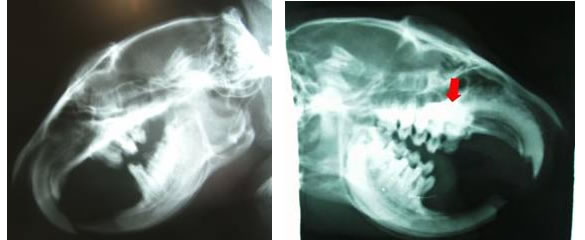

上記の画像はレントゲン画像です。

プレーリードッグの口の中のものです。

左の画像は正常な頭部で右の画像の赤い矢印部分が歯牙種です。

左の画像より赤い矢印部分の方が白い陰影が増していますね。

歯牙種は歯の根っこの部分にコブのような硬いシコリができた状態をいいます。

つまり赤い矢印部分は硬いシコリができているんです。

で、赤い矢印の近くにはプレーリードッグの鼻があります。

歯牙種の刺激によってくしゃみの症状が出るわけです。